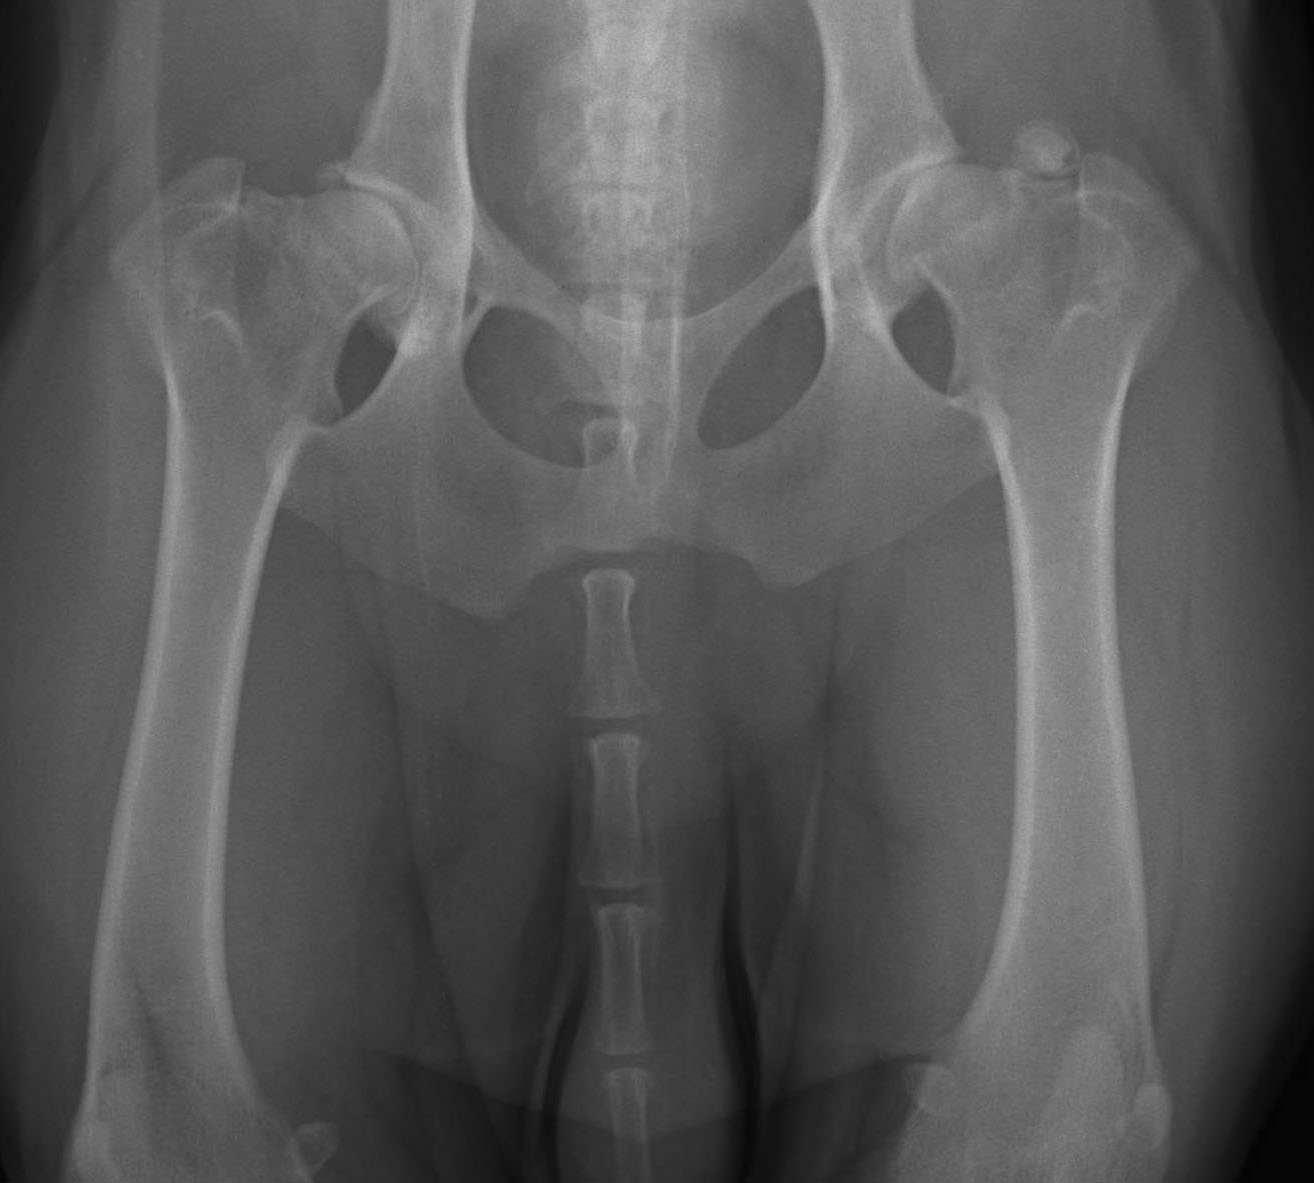

ДТБС у собак: рентгенограммы

ДТБС: степень "B" — в пределах нормы